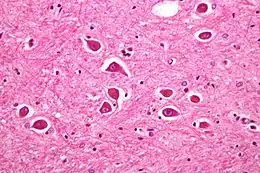

Vue au microscope d'astrocytes de type II, comme en cas d’encéphalopathie hépatique.